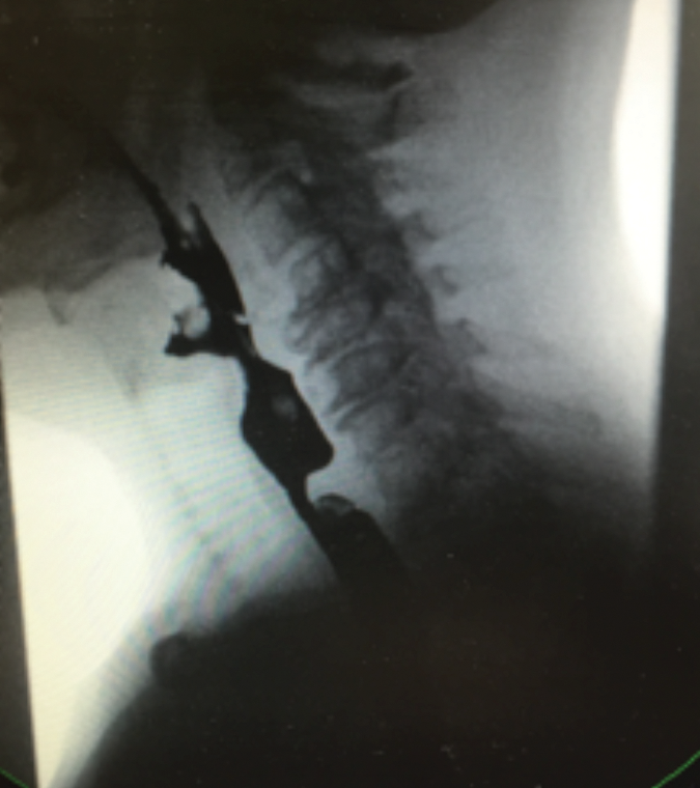

Preoperative preparations: Full clinical history and examination is essential. The importance of patient selection based on symptoms, examination findings and diagnosis from Barium swallow (see Figure 2) and TNO findings cannot be overemphasised.

Figure 2. Barium swallow showing a thick cricopharyngeal bar as the cause of patient’s dysphagia.